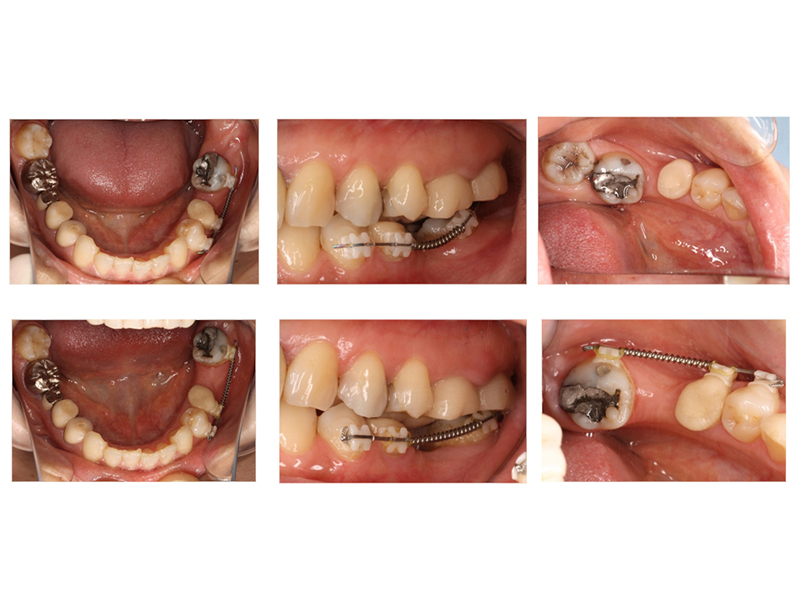

▼ ケース6.矯正的挺出

矯正開始前

矯正開始

矯正終了

補綴終了

矯正開始前、矯正終了時、補綴終了